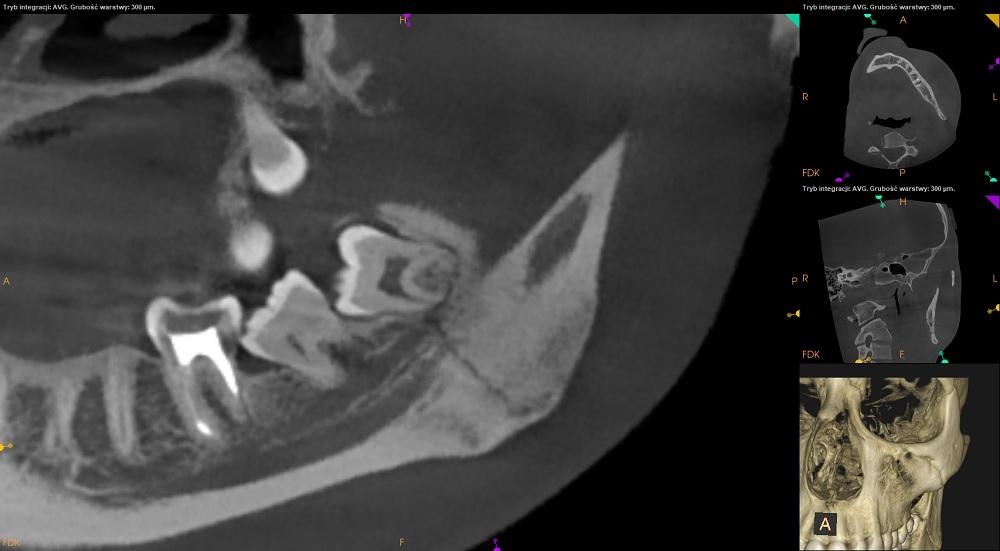

W kości żuchwy widoczna szczelina złamania bez przemieszczenia odłamów w okolicy kąta żuchwy po stronie lewej oraz szczelina pęknięcia w okolicy 43-44

– do konsultacji na oddziale chirurgii szczękowo-twarzowej.

Objęta blaszka zbita po stronie policzkowej i językowej oraz tylna krawędź gałęzi żuchwy.